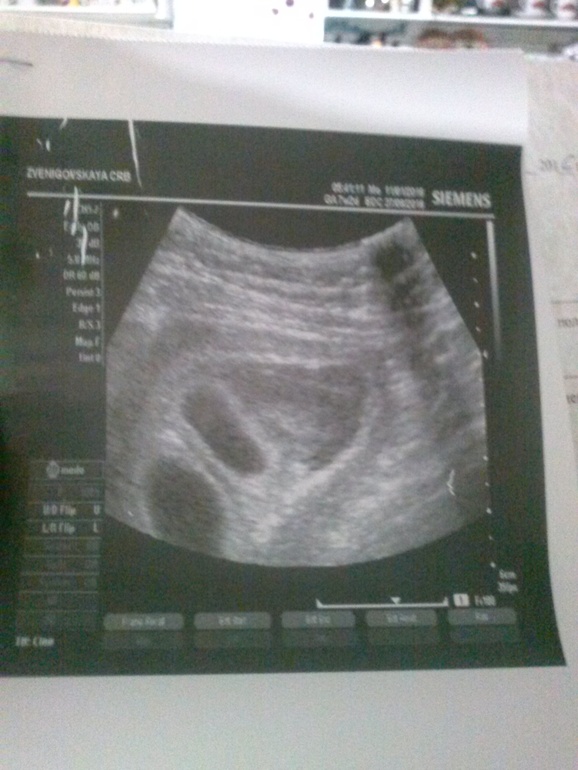

На мой взгляд двойная, но я бы лучше сходила в клинику с нормальным оборудованием.

На фото-двойня!!!и геиматому видно..немаленькая... Дай боже,чтоб все было хорошо!!!